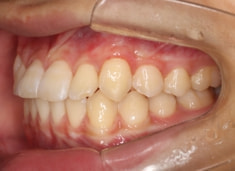

治療前

治療開始時